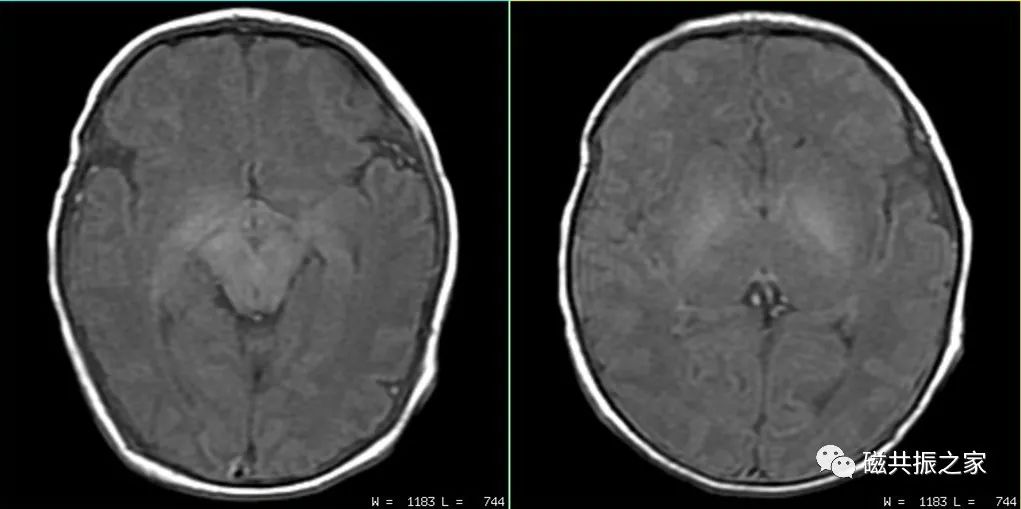

患儿4d,T1WI△,TR=500ms,TE=20ms,1.5T。如使用与成人相同的扫描参数很难获得优异的对比图像。应适当的延长TR值获得优异的图像对比,新生儿最长TR可设置到1000ms左右,随着年龄的增长TR值可逐渐降低,通常到两周岁时可与成人的TR值类似。

患儿4d,T1WI IR△,1.5T。

左:TR=1750ms,TE=20ms,TI=750。

右:TR=2200ms,TE=20ms,TI=850。

随着主磁场强度的增加,组织的T1值会延长,脑灰白质对比度会逐渐降低,为了获得优异的T1对比图像,建议使用T1WI IR序列扫描。